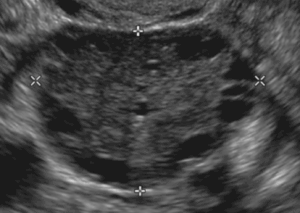

임신 초기 성병 검사가 반드시 필요합니다.

임신 중 성병, 무증상이라도 꼭 검사하고 치료해야 하는 이유를 알고 계신가요? 태아에게 치명적인 영향을 줄 수 있는 주요 생식기 감염병에 대해 알아보고, 건강한 임신을 위한 필수 정보를 확인하세요.

임신초기신체변화

임신 초기에 나타나는 다양한 신체 변화와 여성이 겪는 증상, 그리고 반드시 병원에 가야 할 위험 신호까지, 임신부에게 필요한 정보를 담았습니다.

임신 초기 성병 검사가 반드시 필요합니다.

임신 중 성병, 무증상이라도 꼭 검사하고 치료해야 하는 이유를 알고 계신가요? 태아에게 치명적인 영향을 줄 수 있는 주요 생식기 감염병에 대해 알아보고, 건강한 임신을 위한 필수 정보를 확인하세요.

임신초기신체변화

임신 초기에 나타나는 다양한 신체 변화와 여성이 겪는 증상, 그리고 반드시 병원에 가야 할 위험 신호까지, 임신부에게 필요한 정보를 담았습니다.